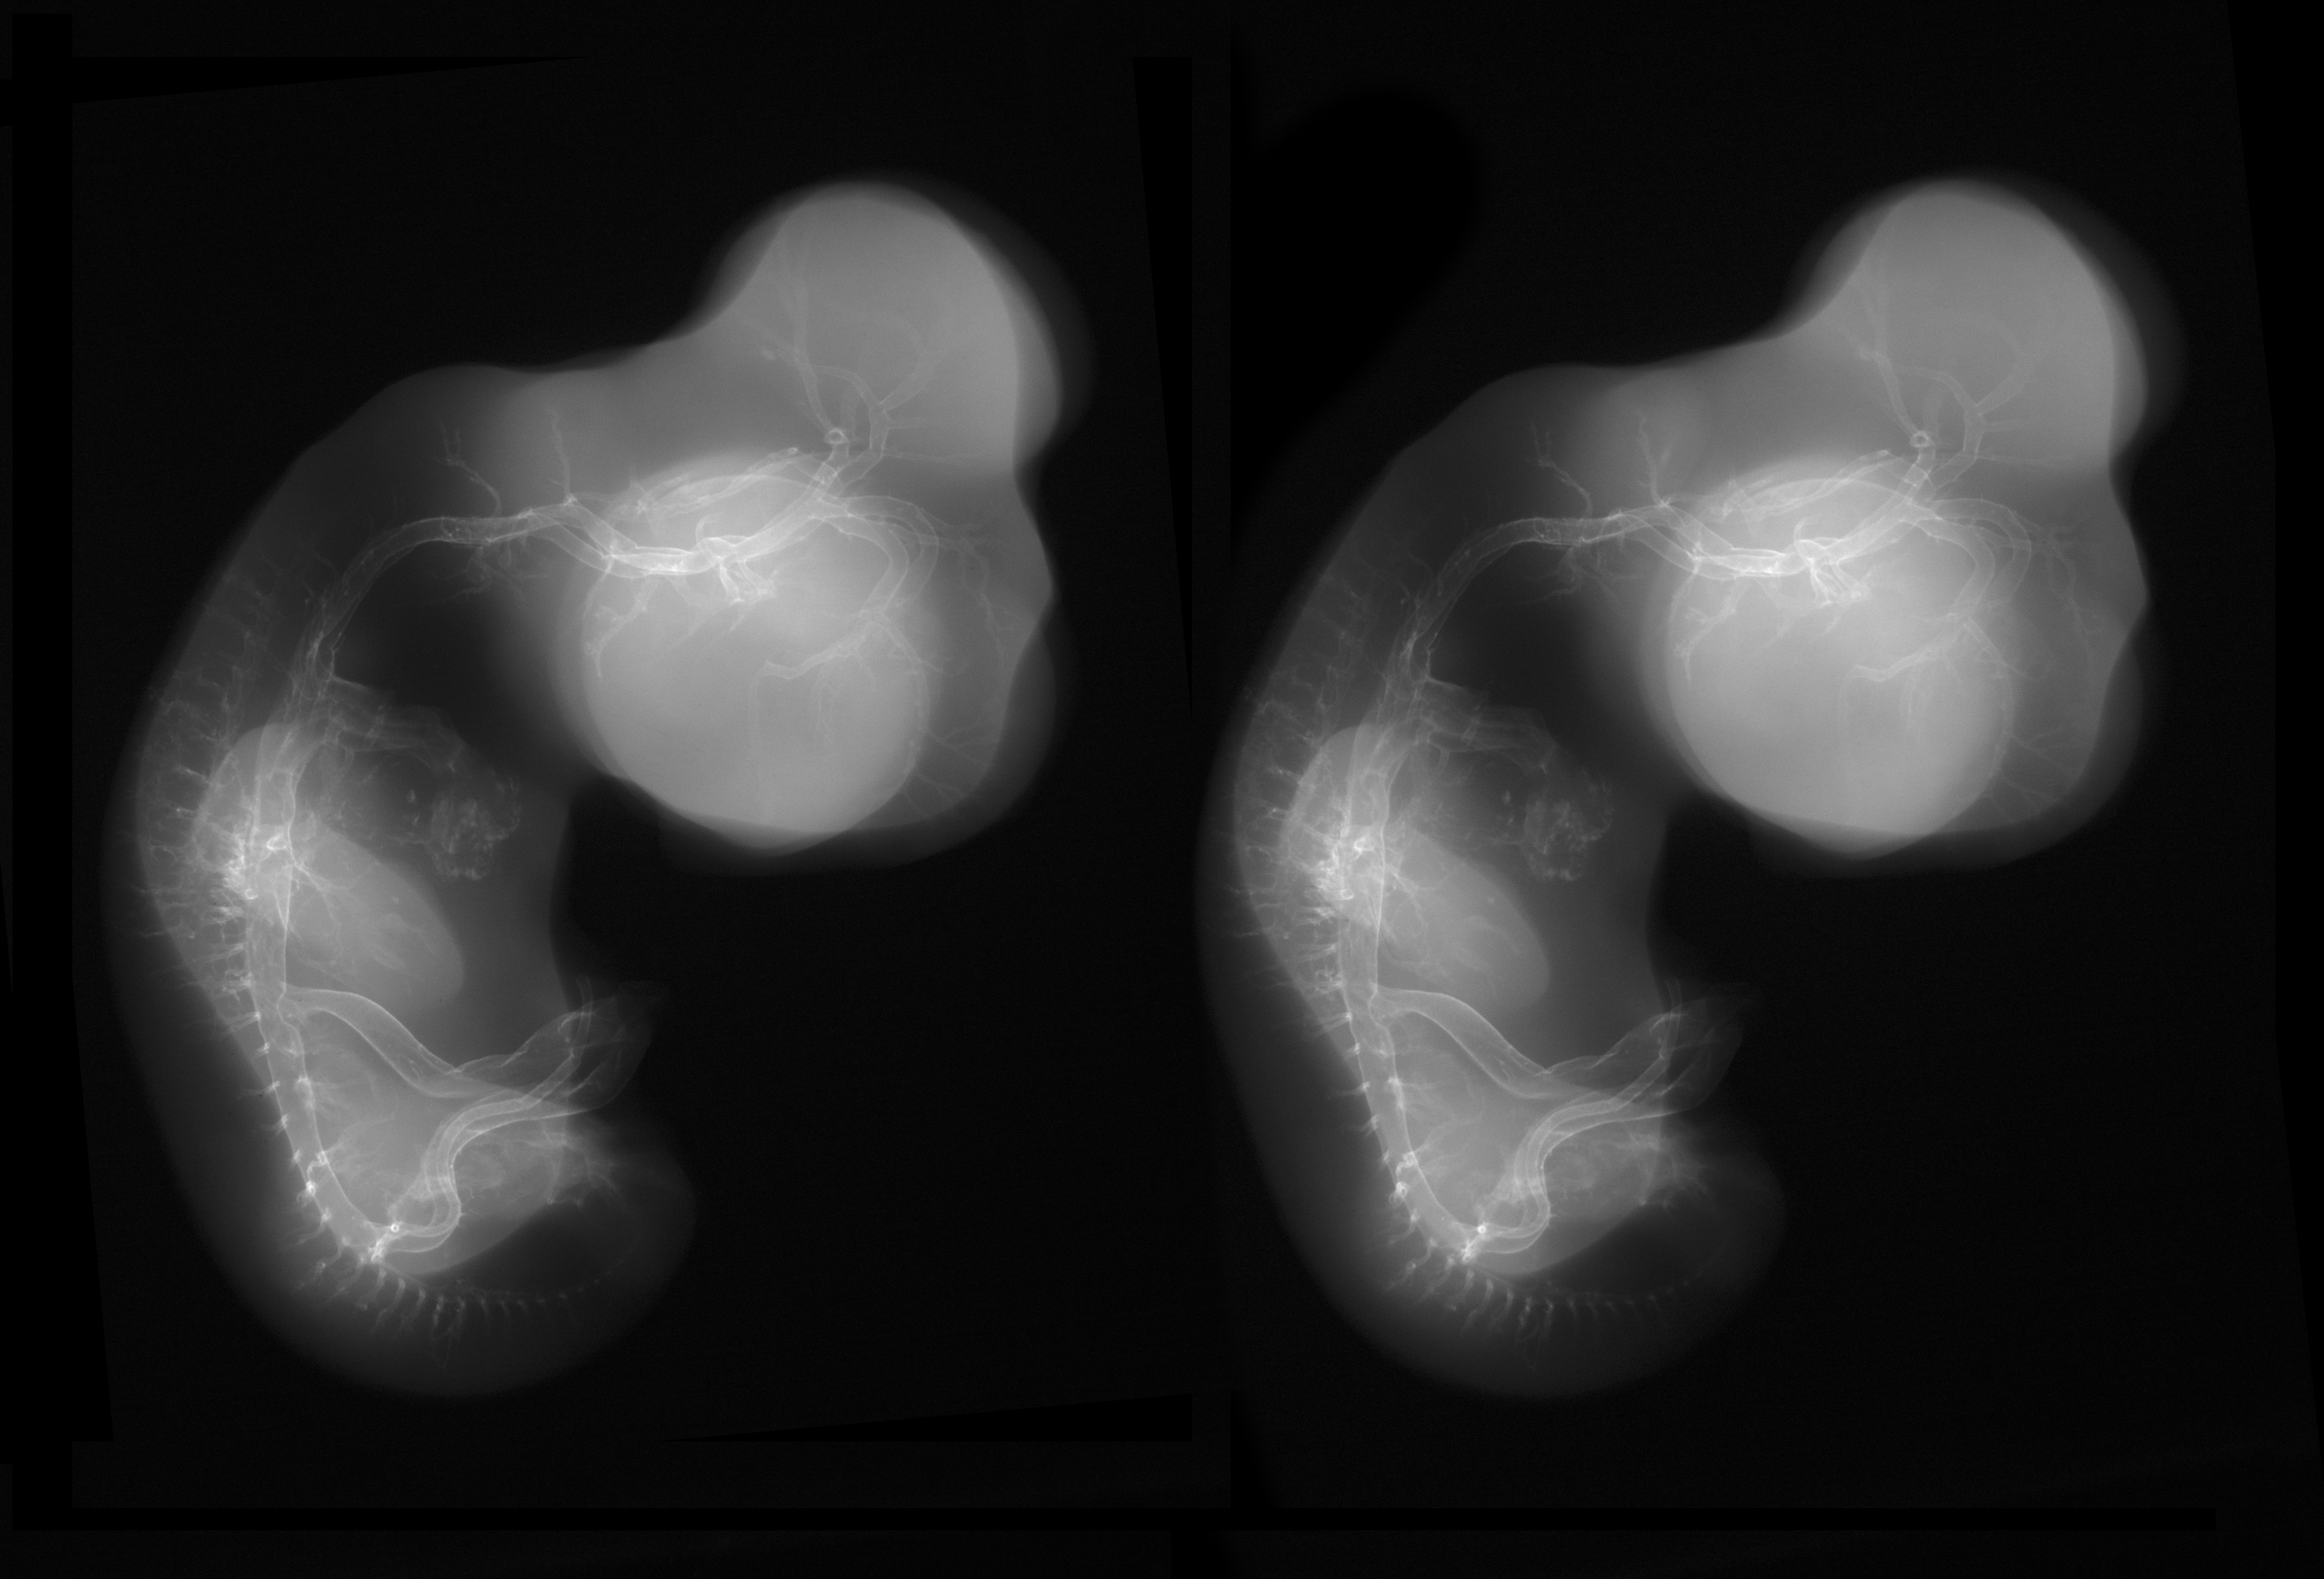

Stereo X-Ray Micrographs